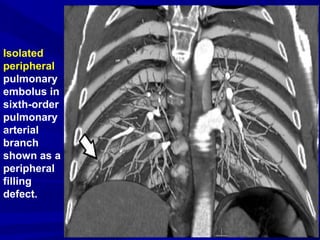

Isolated

peripheral

pulmonary

embolus in

sixth-order

arterial

branch

shown as a

filling

defect.